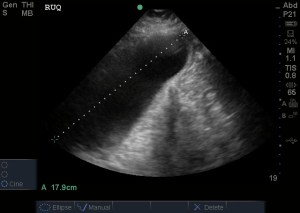

RUQ view:

There was no free fluid seen and no hydronephrosis on the right (another image not posted had no evidence of pleural effusion). But….instead of going to the thoracic views, another RUQ view was obtained for better visualization, but something else appears in the image, noticed by the residents that has them want to explore more….

They noticed the gallbladder and how abnormal it appeared, with possible pericholecystic fluid in the above clip, so they went on to evaluate it: